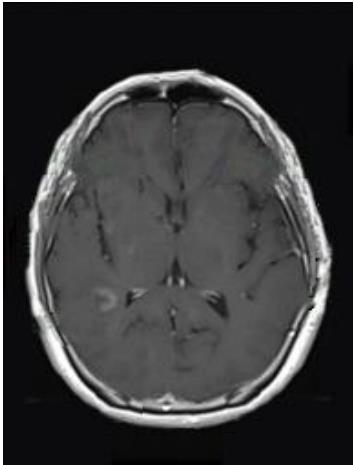

• 肿瘤样脱髓鞘病变报道3例

2023, 48(5):614-617. DOI: 10.13406/j.cnki.cyxb.003183

摘要 (95) HTML (24) PDF 1.29 M (241) 评论 (0) 收藏

摘要: